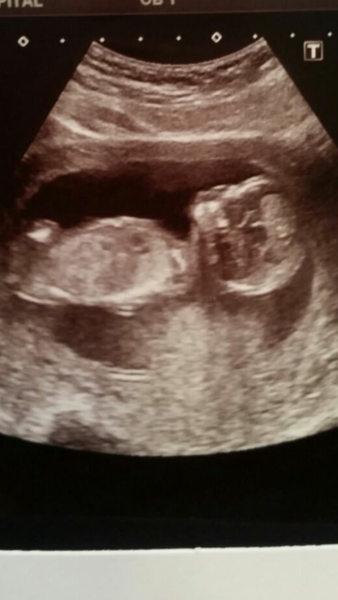

Q yay!!!! So happy for you, what a great pic